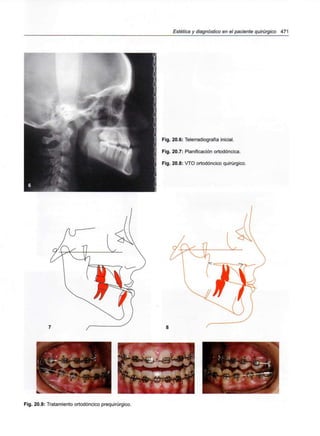

Capítulo 20 - Estética y diagnóstico en el

paciente quirúrgico 469

Diagnóstico 476

Examen facial clínico y fotográfico 480

Estudios cefalométricos utilizados en

los pacientes quirúrgicos 484

Análisis sagital del perfil 494

433 Capítulo 22 - VTO ortodóncico-quirúrgico 521

1a Etapa: Planificación ortodóncica 521

2 Etapa: Planificación quirúrgica 525

VTO ortodóncico-quirúrgico 525